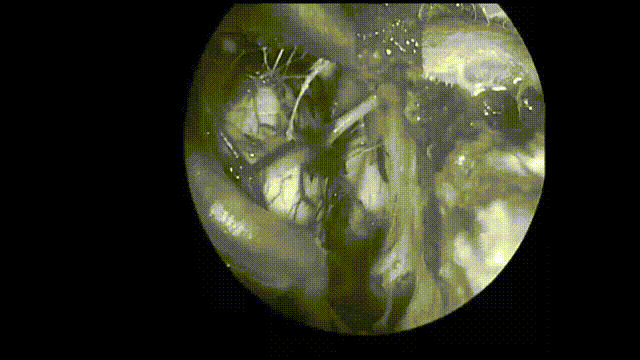

▼内镜检查,向下查看颅颈交界区。内镜探查看到少量肿瘤残留,稍后将用显微镜进行处理。仔细检查完成后,借助内镜取出视觉盲点处的肿瘤残余。